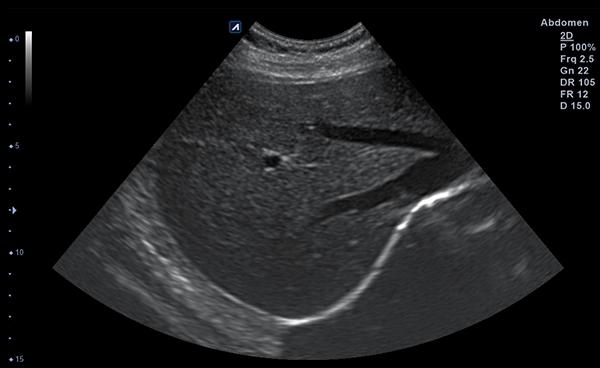

Alpinion Medical Systems, la empresa de sistemas de ultrasonido, ha combinado tecnologías

de procesamiento de imágenes y transductores para garantizar que minisono proporcione

imágenes 2D de alta definición e información de Doppler más claras y nítidas.

Con Convex y Linear, dos tipos de transductores, puede escanear tanto las

partes más superficiales como las más profundas del cuerpo humano.

Los transductores tienen un amplio rango de aplicaciones y pueden ser utilizados en

una gran variedad de situaciones clínicas.